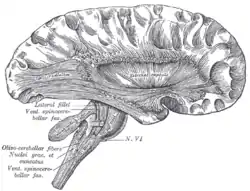

Superficial dissection of brain-stem. Lateral view.

Superficial dissection of brain-stem. Lateral view. Superficial dissection of brain-stem. Ventral view.